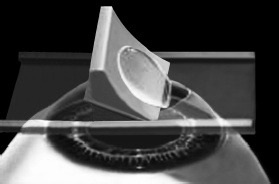

Итак, головка присоединяется к вакуумному кольцу и по специальным полозьям двигается над куполом роговицы (рис. 3). Срез, или отслаивание (называйте, как хотите), проводится не полностью, у крышечки (роговичного лоскута) остается маленький участок на периферии, соединяющий ее с роговицей (рис. 4).

Рис. 4. Роговичный лоскут сформирован.

Иллюстрация с сайта Международного лазерного центра www.optics.ru